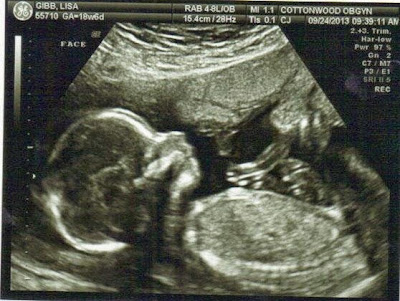

We found out yesterday, September 24th, that our next sweet baby will be a girl! We are SO excited! The ultra sound went great. She is healthy and happy and so very wiggly! We felt so much relief in being able to see her and know she is okay. With this knowledge under our belts we felt like it was finally the time to let everyone know we that we are expecting, it's been so fun to have so many people share our excitement with us! We have felt so much love!

The nausea has slowly gone away, it ended around what we thought was my 17th week but it turns out I was only 16. I would have been 19 weeks today but after the ultra sound and all the measurements they took it looks like I'm only 18 weeks. My due date was pushed back to February 27th and it doesn't bother me one bit. We are so happy to know that she is healthy and that she is a she! Gavin has told us without hesitation that we would be having a girl, I love that he was right! We love her so very much!

Baby Girl - Almost 18 weeks